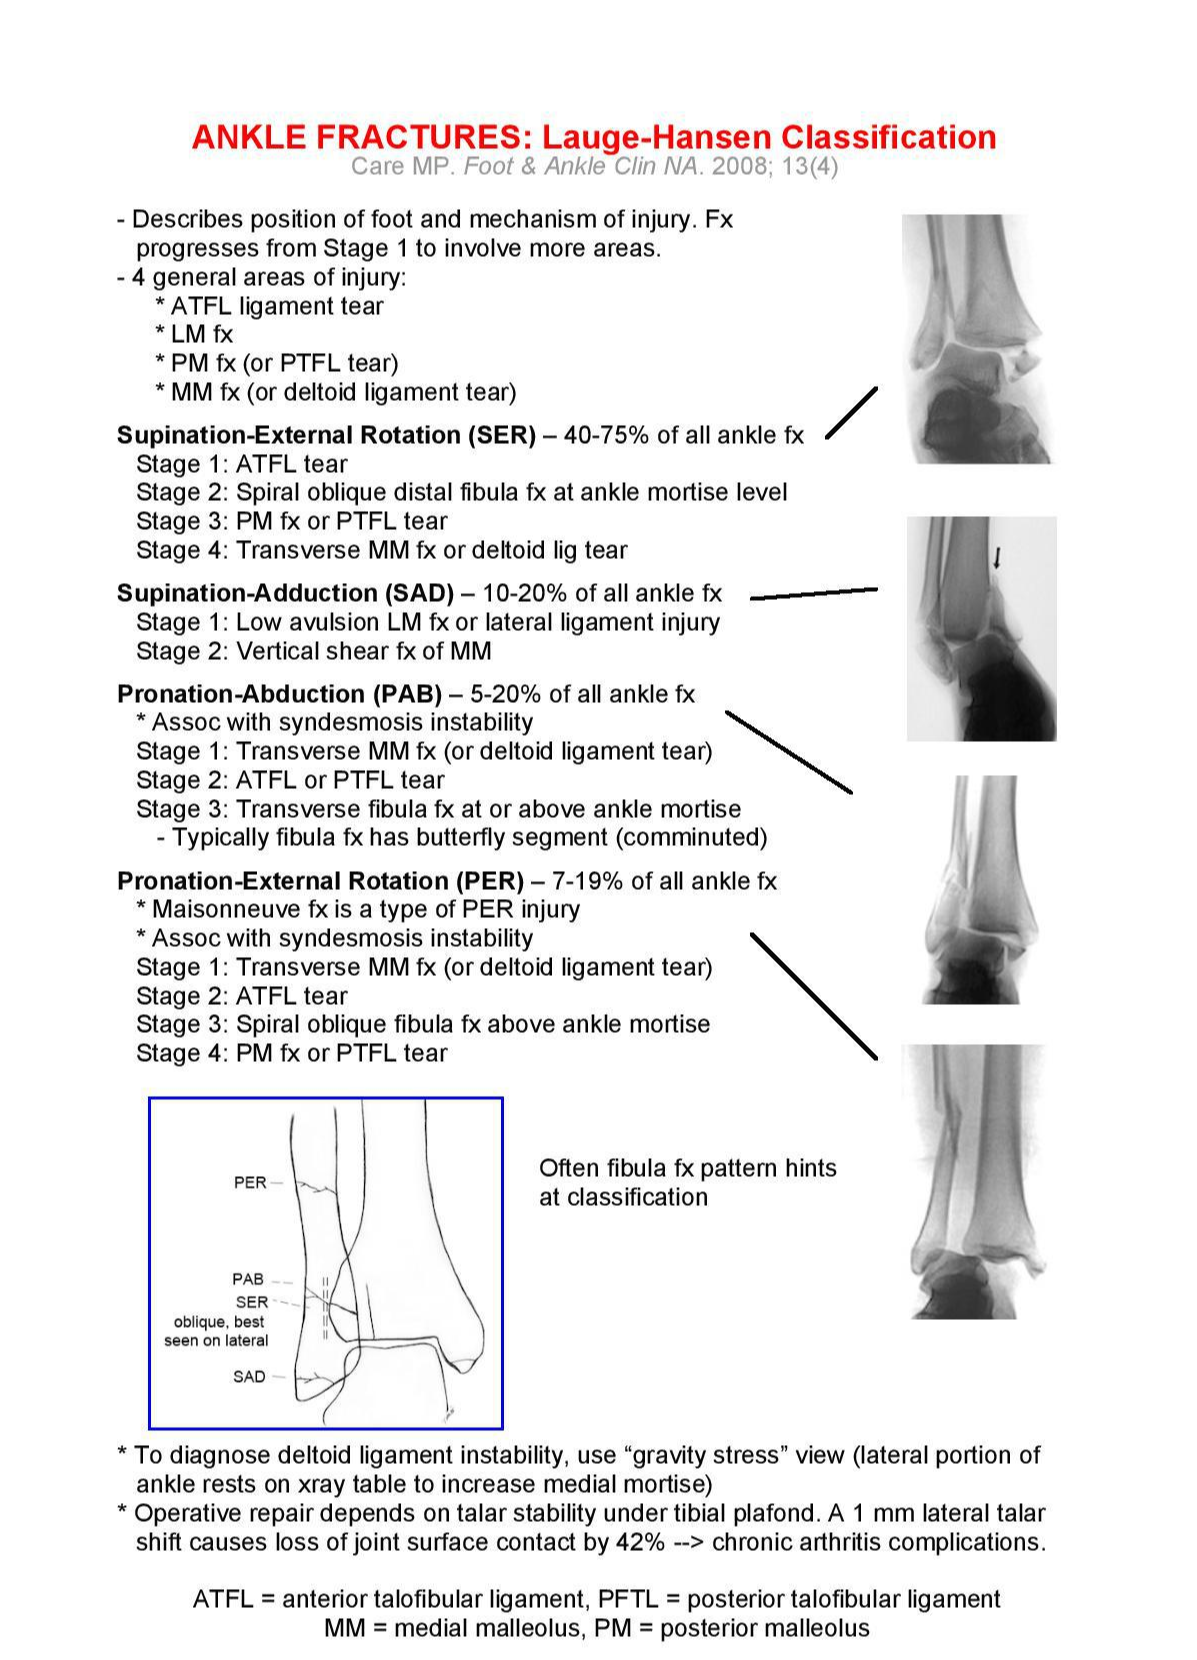

'Weber type 과 Lauge-Hansen' type 입니다. 이 것들은 손상의 정도나 매커니즘을 유추할 수 있지

높이에 따라 A, B, C 로 나눌 수 있고 B의 경우 경골과 비골이 연결되는 연결인대가 손상되는 경우에 해당됩니다. Lauge Hansen은 골절의 회전방향이나 발의 방향에 따라 손상되는 것을 파악하게 되는데, 나중에 나오겠지만 비골의 높은 골절이 동반되는 경우 PER type 인 경우가 많습니다.

크게 Supination과 Pronation 으로 나누고 그 안에서 adduction, ER type / Abduction, ER type 으로 각각 나뉩니다.

Fibula Transverse 한 fracture의 경우 : Supination Adduction 인 경우가 많으며

Vertical medial malleolus Fx 도 Supination Adduction 입니다.

Fibular fx Oblique 전하방 -> 후상방 골절선인 경우 : Supination External Rotation 인 경우가 많습니다.

관절면 8~9cm high fibula fx type의 경우 : Pronation External Rotation 인 경우가 많습니다.

관절면 1cm 위인 경우 or fibula Comm Fx. Pronation Abduction

Supination의 경우 주로 비골의 손상이 먼저 동반되게 되며, Pronation 의 경우 Medial malleolus 부위가 먼저 손상 받습니다. Tibia lat 면에서 생기는 Chaput fragment 는 Pronation 에서 생깁니다.

정리해보면 SER, SAD, PAB, PER 로 나뉠 수 있으며 손상순서가 생각보다 중요합니다.